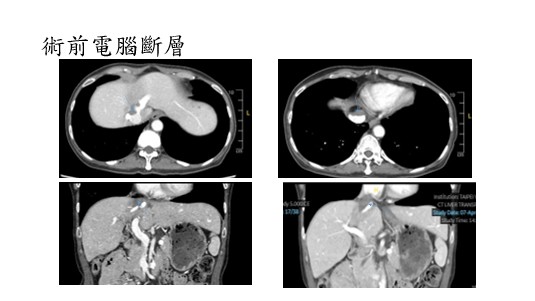

113年6月,53歲潘女士在例行健檢發現體內一顆惡性腫瘤(圖一),病理報告說是「惡性平滑肌肉瘤」,盤根錯節緊緊扼住肝靜脈與下腔靜脈,直抵心臟。

今年三月,潘女士至臺北榮總一般外科王心儀主任門診,王主任連絡了我,經過一番腦力激盪,決定了手術方式(圖二):將肝臟從體內完整取出,在體外進行精準的腫瘤切除與肝靜脈重建;同時,心臟外科團隊啟動體外心肺循環,切除位於下腔靜脈及右心房的腫瘤,並重建下腔靜脈;最後,再將煥然一新的肝臟,重新「歸位」!也許有人覺得這如同電影情節般的天方夜譚,但我跟潘女士說我不想放棄她的治療,也希望她不要放棄自己。